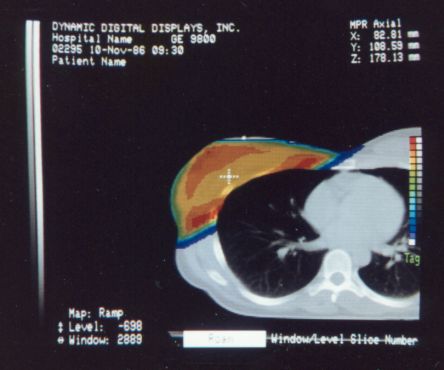

The first workstation to be seriously marketed was Voxelscope II (VS2) which had greatly enhanced volume memory and higher display resolution. Unfortunately, that came at a cost and it, and all its successors never even came close to achieving the true video-rate real-time performance of the VPP, which would have required the massively parallel technology in the Patent. But even very early on, VS2 had somewhat real software with a Graphical User Interface (GUI) and enough functions to be credible, at least for demos including instantaneous Multi-Planar Reformatting (MPR) which could display a slice though the object at any depth aligned with one of the principal axes (axial, saggital, or coronal) or at an arbitrary angle, as well as real-time (fraction of a second, but not video rate) 3-D shaded surface with density selection and slicing. A Motorola 68000-based VME bus single board computer replaced the PDP-11 or VAX (sorry DEC) and implemented the high level control and Graphical User Interface (GUI), ran the file system, and interfaced to the outside world.

These photos of the Voxelscope II screen are typical of the types of rendering provided by the system.

Voxelscope II Screen Shots. Combination of 3-D Shaded Surface, Multiplanar Reformatting, and Segmentation

Of course, once there was a real Marketing department, the real Software types (led by Eddie Wyatt) were always slowing things down anyhow in the interest of generality - or to concentrate on features users might actually care about! What a conecpt? ;-) One example was Multi-Planar Reformatting or MPR where a single cut along one of the principal planes - axial (XY), saggital (YZ), coronal (XZ) - or at an arbitrary angle or even curved cut through the object is displayed. MPR could have run at full video rates on any of the machines, but no matter how hard I tried to convince Software to improve the performance, it never chugged along at more than a couple frames per second. :( :) And large portion of the VS2 hardware capabilities were never exploited due to feature priority as determined by Marketing.